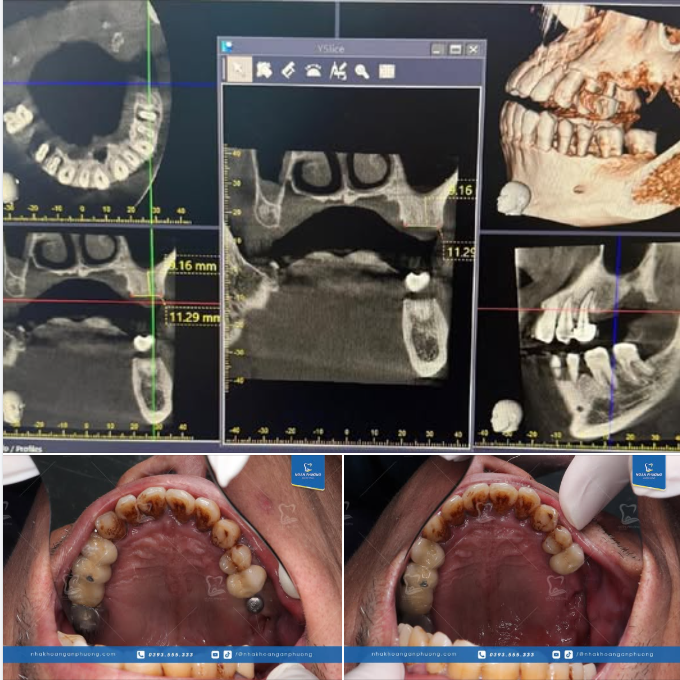

Làm sứ và phục hình implant đã giúp Mai Huyền có được nụ cười mơ ước và răng miệng khỏe mạnh.

Chúc mừng bạn ấy Tết này đã có diện mạo mới và cảm ơn Mai Huyền đã tin tưởng Nha khoa Ngân Phượng ^^ Xem thêm trồng răng implant